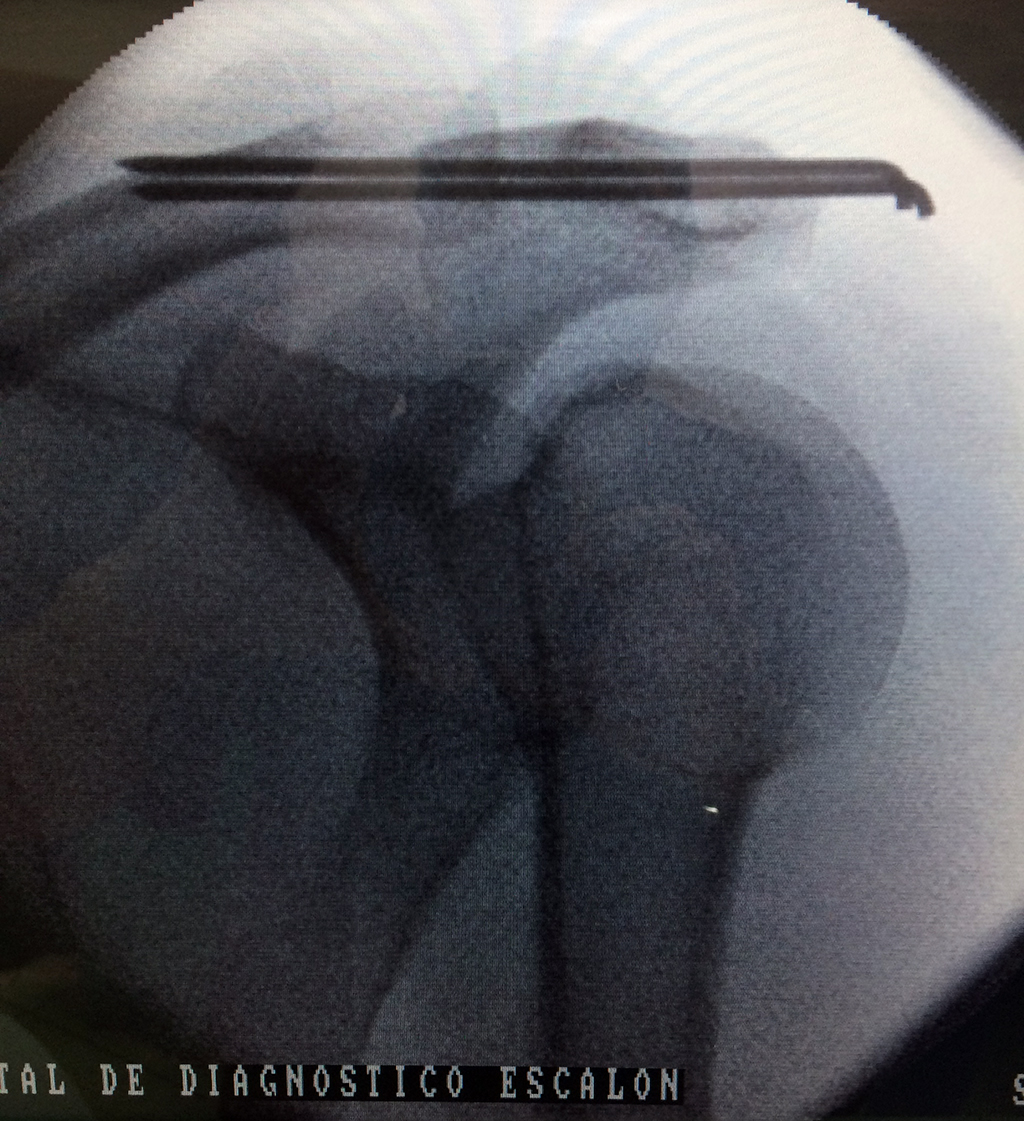

Húmero - Clavícula